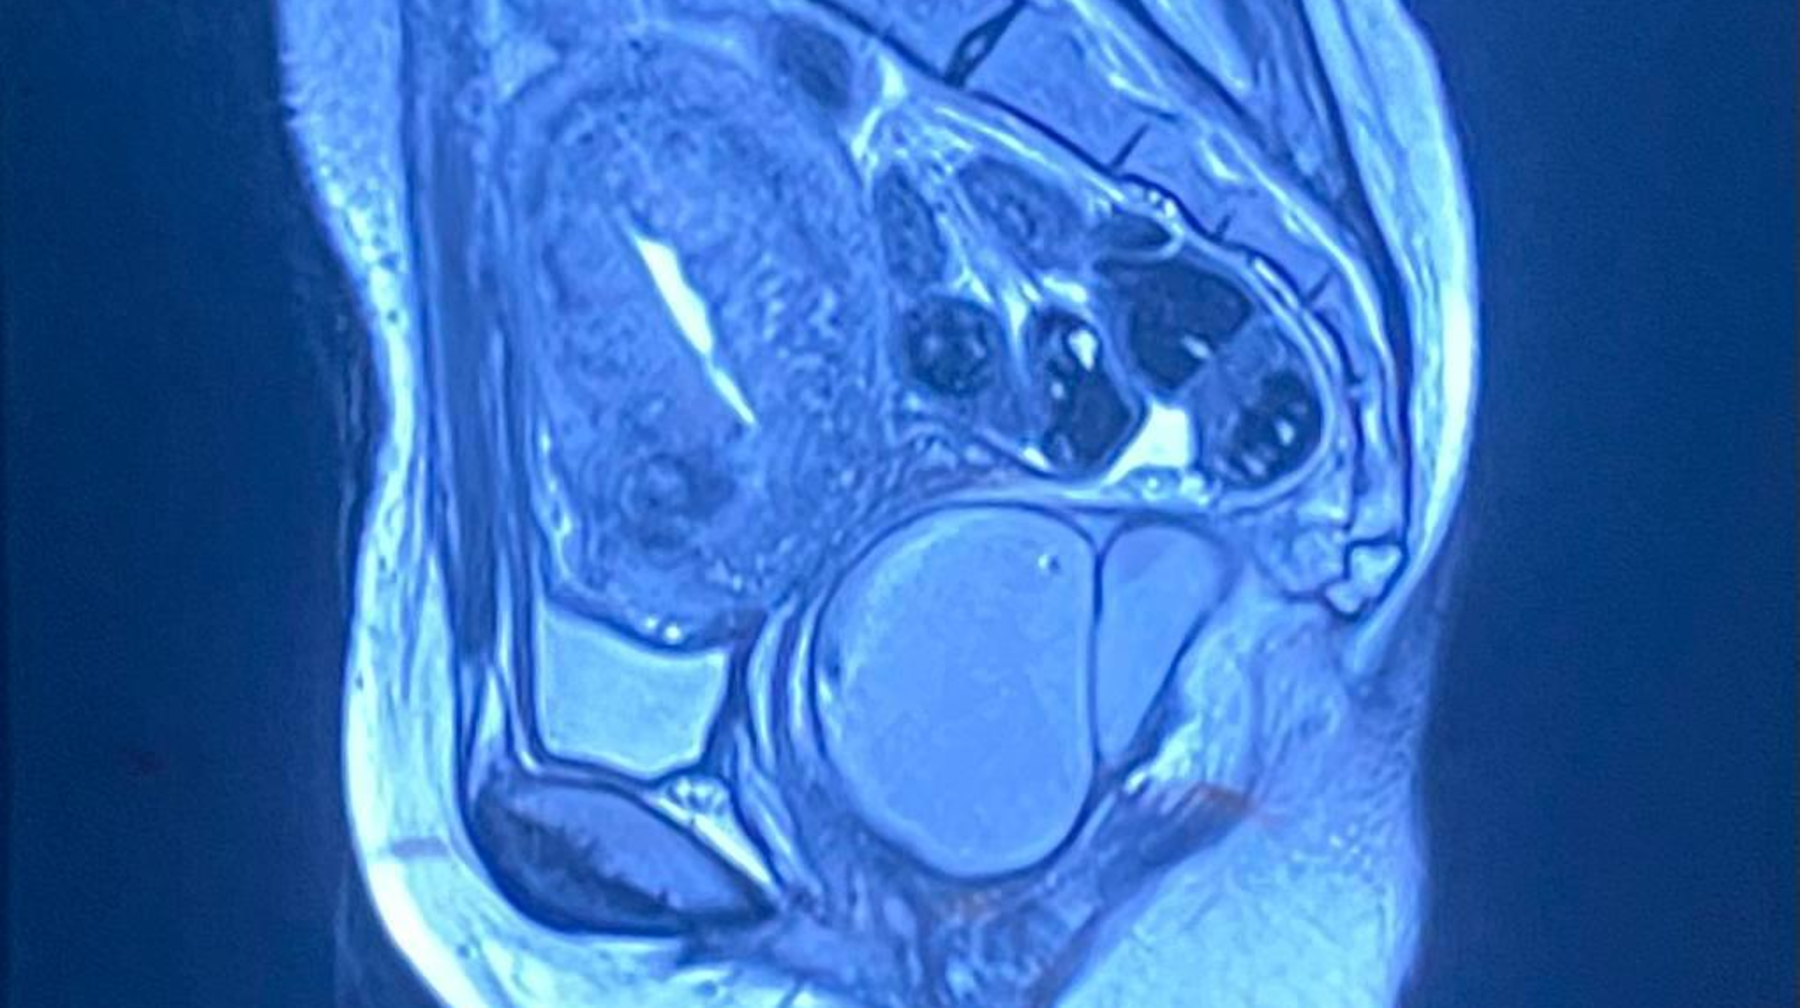

Бас және мойын қатерлі ісіктеріне көмей, синус, жоғарғы және төменгі жақ, ауыз қуысы, жұтқыншақ және сілекей бездері сияқты аймақтардағы қатерлі ісіктер жатады, деп хабарлайды aqshamnews.kz